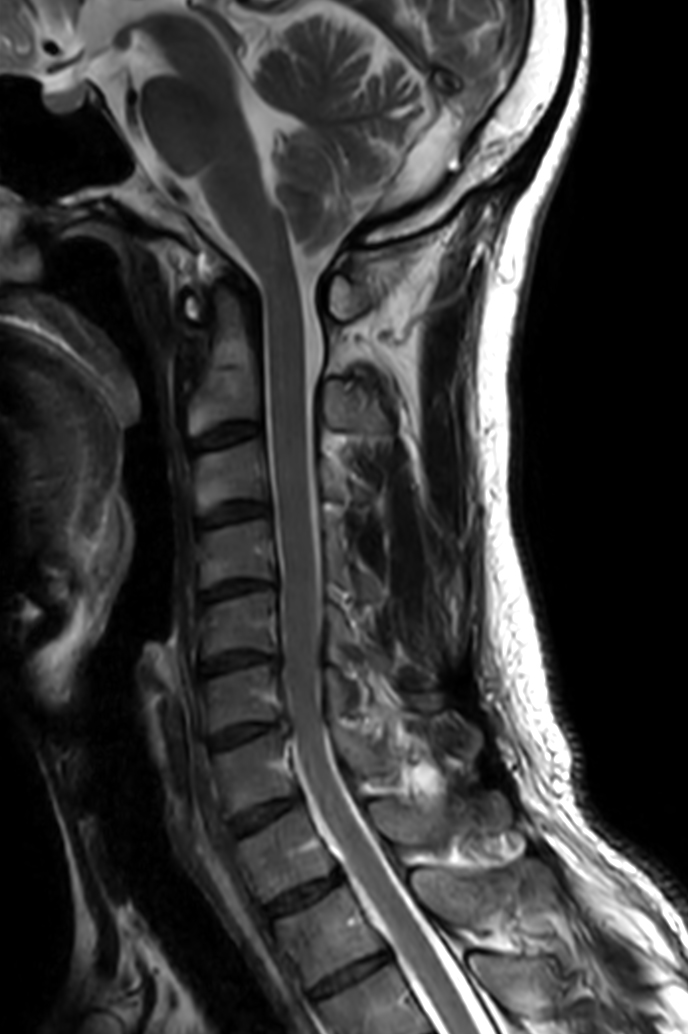

Sagittal T2w TSE

Sagittal T2w TSE - Compressed SENSE